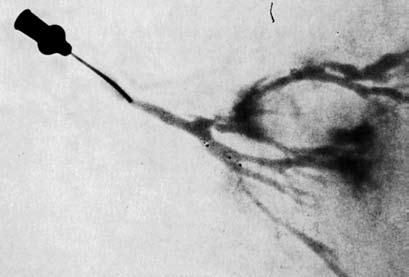

Рис. 11. Дуктограмма: контрастное вещество через выводящий проток попадает в более мелкие протоки молочной железы и окружает там овальное новообразование с неровными контурами

После этого выполняют рентгенографию. Полученные снимки используют для оценки формы и очертаний млечных протоков. Наличие дефектов наполнения просвета протока может свидетельствовать о внутрипротоковом РМЖ (рис. 11).